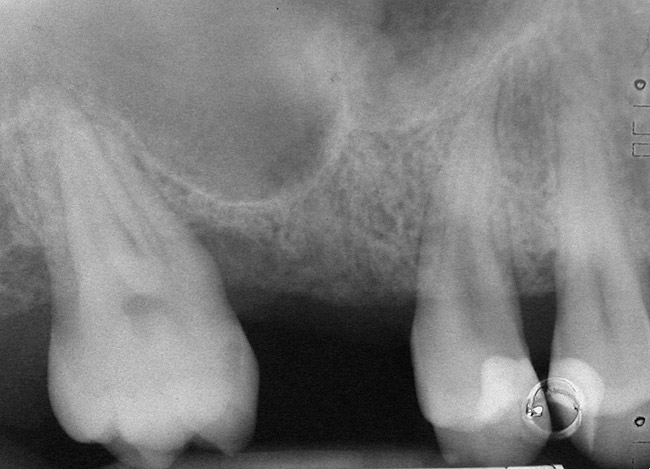

A 45-year-old female was referred for implant placement and prosthetic treatment in the area of tooth No. 24. The tooth had been extracted 4 years prior; the patient did not wear any denture thereafter. The radiograph revealed adequate bone height and a 5-mm to 6-mm ridge at the crest (Figure 2). It was decided to place a 11.5 mm in length, 3.75 mm in diameter Tapered Screw-Vent® implant (Zimmer Dental, www.zimmerdental.com) using the alveolar remodeling technique in the area of tooth No. 24.

Figure 2 Preoperative view of the area around tooth No. 24. On the left, a previously placed implant abutment

is visible.

Figure 2  Preoperative view of the area around tooth No. 24. On the left, a previously placed implant abutment is visible.

Figure 2